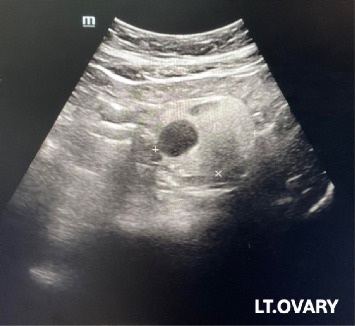

Introduction: Mature cystic teratoma is a common benign ovarian germ cell tumor containing well-differentiated cells from three germ layers. Malignant transformation within these teratomas, such as papillary thyroid carcinoma, is extremely rare. Case Report: A 62-year-old asymptomatic woman was found to have a 5 cm hyperechoic lesion with an internal cystic component in her left ovary, suspected to be a mature teratoma. A total hysterectomy with bilateral salpingo-oophorectomy was performed, removing an unruptured, thin-walled ovarian tumor. Gross pathology revealed a uni-loculated solid-cystic lesion with smooth serosa, a homogenous tan solid part containing soft tan hair, and no papillary projections, adhesions, or ascites. Pathology identified a 2 cm papillary thyroid carcinoma (classic subtype) arising in a 4.7 cm mature teratoma, without lymphovascular invasion or ovarian surface involvement. Thyroid ultrasound, thyroid function tests, and PET imaging showed no abnormalities or metastasis. The role for total thyroidectomy and radioactive iodine ablation was discussed. After reviewing the pathology and confirming the absence of aggressive tumor behavior, shared decision-making led to opting against further treatment. Three years postoperatively, there was no recurrence or metastasis. Conclusions: This case describes the rare occurrence of papillary thyroid carcinoma within a mature ovarian teratoma. Currently, there is a lack of consensus on postoperative management. In selected cases with no evidence of metastasis or aggressive features, conservative management may be a reasonable option after thorough evaluation.